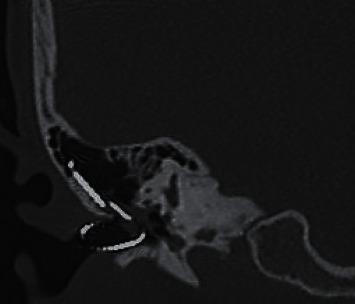

Although rare, cholesteatoma can develop as a late complication of cochlear implantation. The electrode array may then be exposed in the external auditory canal surrounded by cholesteatoma debris. . The cochlear implant of a child was inadvertently explanted by a clinician during a routine aural toilet procedure. The child had previously reported recurrent ear infections, pain, and unexplained implant function degradation. Reimplantation was carried out 2 days later with good postoperative hearing results. Part of the electrode array was observed to be embedded in cholesteatoma. Postreimplantation recovery was complicated by a breakdown of the blind-sac. . Clinical indicators that could alert the clinician to the possibility of this late complication include recurrent infections, presence of keratotic debris in the external auditory canal, unexplained implant function degradation, and nonauditory stimulation. Although this patient managed to achieve excellent postreimplantation hearing outcomes, a delay in reimplantation surgery following explantation could possibly compromise successful reinsertion of the electrode array. External ear canal overclosure without mastoid cavity obliteration has merit in facilitating CT scan surveillance, but it may increase the risk of the blind-sac breaking down. This case also illustrated how the electrode array could have facilitated propagation of the cholesteatoma from the middle ear to the mastoid.

胆脂瘤虽罕见,但可作为人工耳蜗植入的晚期并发症出现。此时电极阵列可能会暴露于被胆脂瘤碎屑包围的外耳道中。一名儿童的人工耳蜗在一次常规耳部清理手术中被临床医生意外取出。该儿童此前曾报告反复耳部感染、疼痛以及人工耳蜗功能不明原因的下降。两天后进行了重新植入,术后听力恢复良好。观察到部分电极阵列嵌入了胆脂瘤中。重新植入后的恢复因盲袋破裂而变得复杂。可提醒临床医生注意这种晚期并发症可能性的临床指标包括反复感染、外耳道内存在角化碎屑、人工耳蜗功能不明原因的下降以及非听觉刺激。尽管该患者在重新植入后听力恢复良好,但取出后延迟重新植入手术可能会影响电极阵列的成功重新插入。不进行乳突腔闭塞的外耳道过度封闭有利于进行CT扫描监测,但可能会增加盲袋破裂的风险。该病例还说明了电极阵列如何促进胆脂瘤从中耳向乳突的扩散。